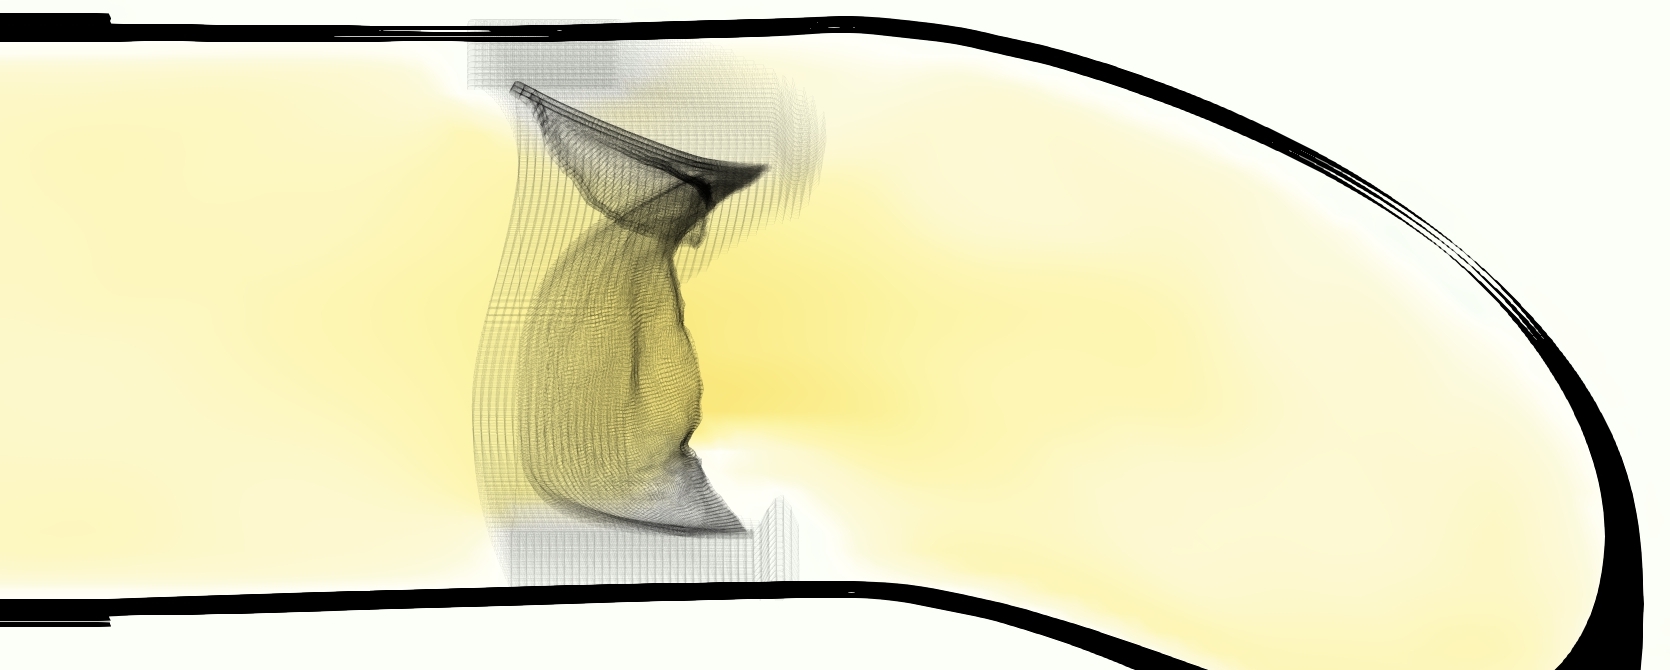

Slice views of the (axial) component of fluid velocity in the axial plane, orthogonal to the flow direction, show that the simulation replicated the development of the jet over the cardiac cycle. At each phase, the simulation matched the forward speed of the core of the jet and the locations of reverse flow back towards the valve annulus. While there are some differences in the shape of the jet at certain phases and locations, the simulation clearly produced the general dynamics of the cardiac cycle that are seen in the experiment.

At = 0, the axial slice directly at the valve annulus shown in columns 1 and 2 in Figure 6, there was excellent agreement between the simulation and experiment over the cardiac cycle in the speed and shape of the jet through the valve. In both cases, the axial velocity increased as the flow accelerated during systole and the valve leaflets opened, then decreased during diastole with slight negative velocity before the valve leaflets were fully closed. The forward flow through the valve annulus did not form a full circle, but rather developed a triangular shape with a point of the triangle forming along the interior curve of the vessel, at the bottom of the axial slices. At = 0, the points of this triangular jet shape aligned with the commissures of the valve. This shape persisted during peak systole and was well-matched by the simulation.

The axial slice = 0.625 cm, shown in columns 3 and 4 in Figure 6, cut through the support scaffolding of the valve and the leaflets when they are open. In the experimental data, the shape of the jet changed as it moved downstream. A triangular shape occurred, but the points were then aligned with the middle of each open leaflet as opposed to the commissures. Those points were also more rounded than they were at = 0. The peak velocity of the jet was faster at = 0.625 cm than at = 0, as the flow accelerated through the open valve leaflets. The simulation produced these features at = 0.625 cm. The triangular shape of the jet shifted similarly, and its speed increased compared to the upstream slice. As the flow decelerated into diastole, the jet shape remained roughly triangular but diminished in intensity before disappearing after valve closure.

The jet continued to develop at = 1.25 cm, an axial slice immediately downstream of the valve scaffolding and open leaflets, shown in columns 5 and 6 in Figure 6. In the experimental data, the points of the triangular jet shape extended further towards the vessel wall. In addition, regions of reversed flow developed in the locations downstream of the commissures, resulting in curved sides to the shape of the jet. Each tip of the jet was unique, due to variations in the individual leaflets in the physical bioprosthetic valve. These variations are apparent in the velocity fields, possibly because the jet edges are similar enough cycle to cycle that irregularities are still being captured even with phase averaging. Further discussion of these features can be found in Schiavone et al. [39], which showed that the jet tip shapes occurred in different pulmonary anatomies, demonstrating that they were likely due to inherent properties of each leaflet. The leaflets in the mathematical model of the valve are identical, so these nuances in leaflet variation could not be replicated. The simulation did capture some of the extension of the tips of the jet, as they were closer to vessel wall at slice = 1.25 cm than = 0.625 cm. The curves in the triangular sides of the jet were also present in the simulation, though they were less pronounced than the experimental data. At both = 0.625 cm and = 1.25 cm, the jet shape in the simulation was smoother than the jet in experiment. It is possible that the free edges of the leaflets in the mathematical model are not fully replicating the behavior of the physical leaflets of the bioprosthetic valve, in particular the amplitude or frequency of leaflet flutter, leading to the variations seen in the jet shape at = 1.25 cm downstream of the leaflet edges. The simulation, however, does capture the key features of the triangular shape and speed of the jet. Overall, qualitative comparisons demonstrated that the simulation reproduced key features of the flow during systole and diastole.